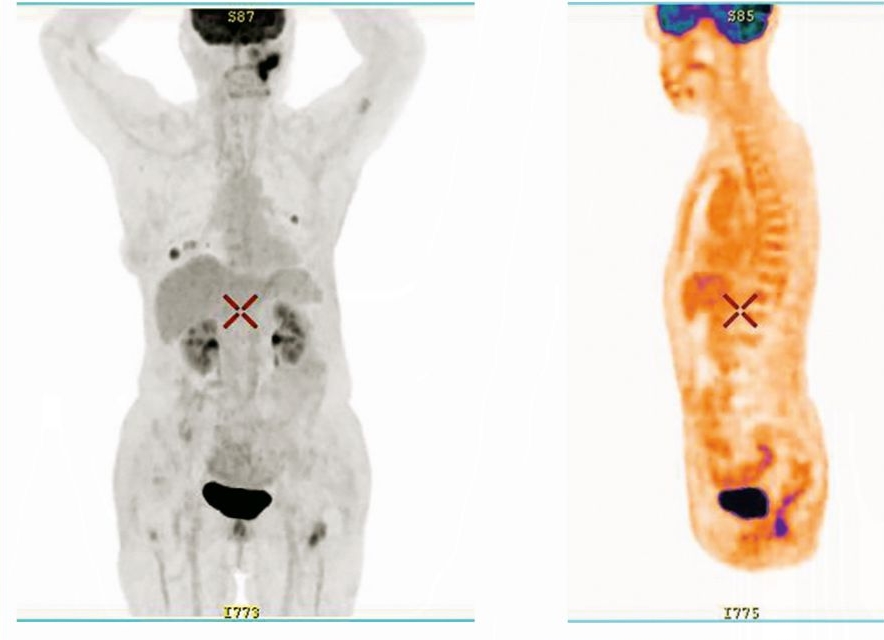

С апреля 2021 г. назначена терапия алпелисибом в комбинации с фулвестрантом (в качестве 7-й линии ЭТ). По результатам ПЭТ/ КТ от августа 2021 г. на фоне терапии алпелисибом отмечена положительная динамика – ЧО. С октября по декабрь 2021 г. пациентка прервала терапию алпелисибом в связи с коронавирусной инфекцией. По данным ПЭТ/КТ от декабря 2021 г. в сравнении с ПЭТ/КТ от августа 2021 г. отмечена отрицательная динамика опухолевого процесса. Учитывая ограниченность возможных лекарственных опций, принято решение о возобновлении терапии алпелисибом в комбинации с фулвестрантом в прежнем режиме. На фоне терапии отмечено клиническое улучшение общего состояния пациентки. По данным ПЭТ/КТ от июня 2022 г. продолжалась стабилизация заболевания: в динамике сохранялись множественные очаги в легких с умеренным снижением активности фтордезоксиглюкозы, в сегменте SIV левого легкого очаг размерами 13×10 мм, SUVmax 3,74 (ранее 16×10 мм, SUVmax 4,74), в сегменте SIX правого легкого до 17×14 мм, SUVmax 5,01 (ранее SUVmax 5,11), в динамике очаг в левой плечевой кости стабилен SUVmax 2,21 (ранее 2,35), очаг в левой бедренной кости SUVmax 4,83 (ранее 3,91), очаг в правой подвздошной кости SUVmax 2,6 (ранее 4,73). Терапию продолжили, при контрольных исследованиях от 15 декабря 2022 г. и 17 июня 2023 г. получены ЧО, 20 ноября 2023 г. ЧО сохранялся. Суммарная продолжительность лечения алпелисиб + фулвестрант составила 33 мес (рис. 6, 7).

Рис. 6. ЧО на терапию алпелисиб + фулвестрант по данным ПЭТ/КТ: определяются метастатические очаги в легких, в левой плечевой кости, в левой бедренной кости и в поясничном позвонке.

Fig. 6. PR for alpelisib + fulvestrant therapy according to PET/CT: metastatic lesions in the lungs, in the left humerus, in the left femur and in the lumbar vertebra are determined.